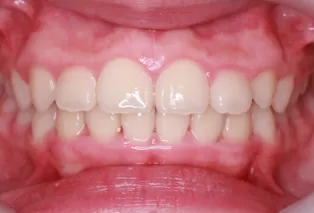

Photos intra-orales